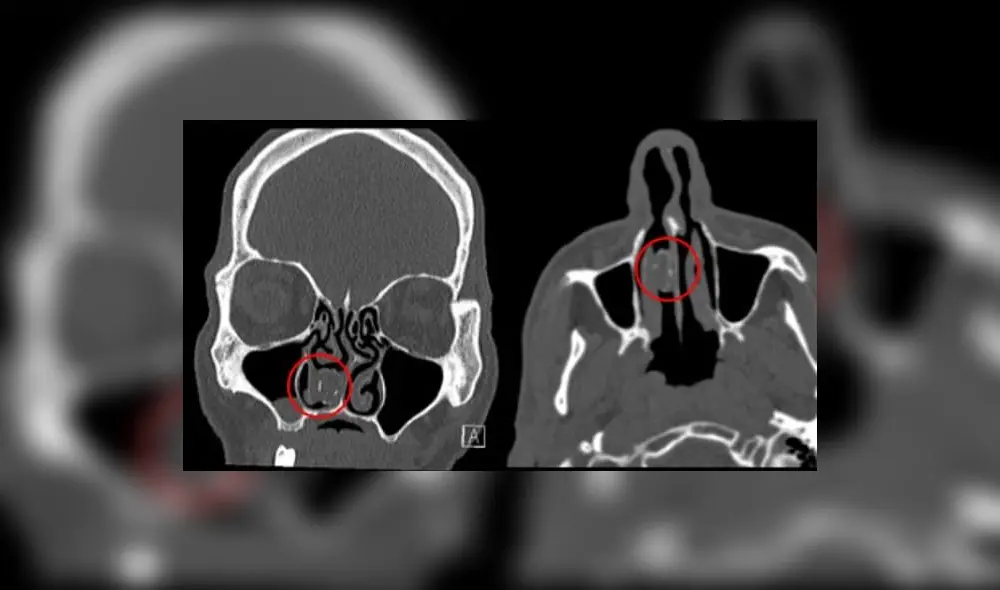

Los médicos de Australia realizaron una tomografía computarizada de su cerebro, luego de que se quejara por severos dolores de cabeza, un síntoma común de este mal.

Mostraba una lesión gris de 1.9cm x 1.1cm en su cavidad nasal derecha y fue derivado al departamento de oídos, nariz y garganta del Hospital Westmead, en Sydney.

El informe del caso, reseñado por la revista BMJ, indica: “Describimos el caso único de un rinolito que se desarrolló a partir de un globo lleno de marihuana que el paciente intentó pasar de contrabando a una instalación correccional”